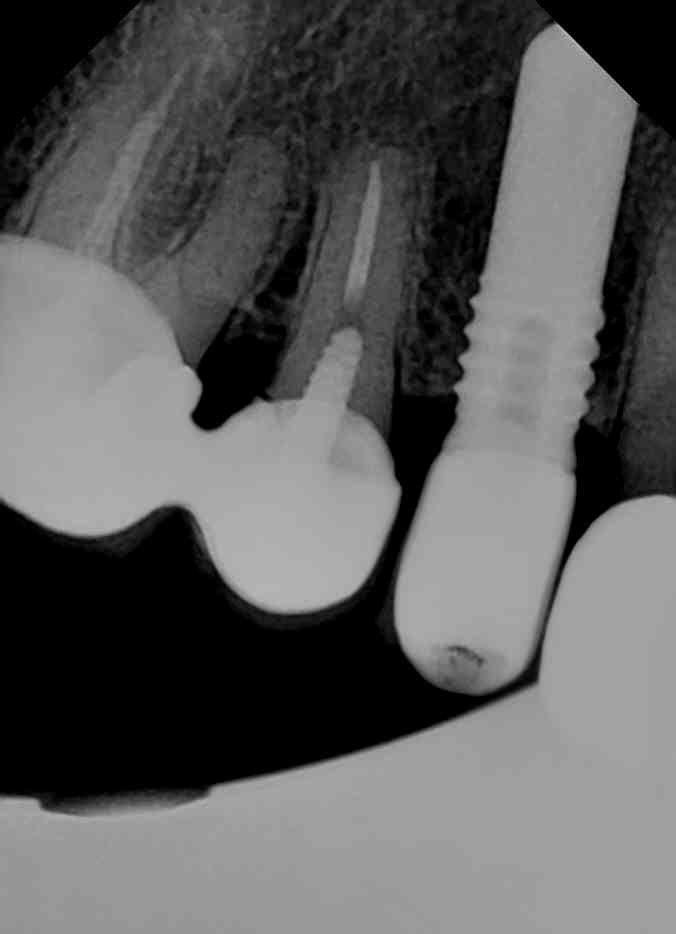

Por favor a ver si alguno sabéis cual es el implante del 12. El paciente se lo colocó en otra clínica y han desaparecido. Conexión interna pero cuadrada (os mando [...]

Buenas, me han enviado un implante de clÍnica y me piden que le diga que conexión es y que pidamos nosotros el tornillo. El caso es que no sabemos cual [...]